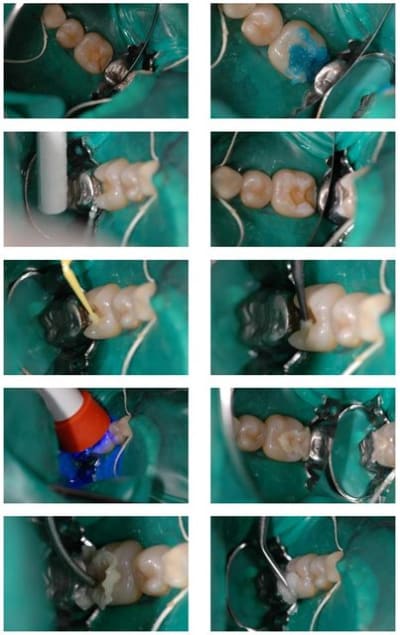

si hombre y en photographias

pour savoir si oui ou non je pouvais le faire, il m'a suffit de faire l'expérience que je joins sur les deux photos.

mes inlays faisant rarement plus de 3 millimètres d'épaisseur, je suis très en dessous des 6 millilmètres de polymérisation que je peux obtenir avec ma lampe et mon composite.

Belle photos didactiques, mais,

ooops avec les photos ça parle encore plus